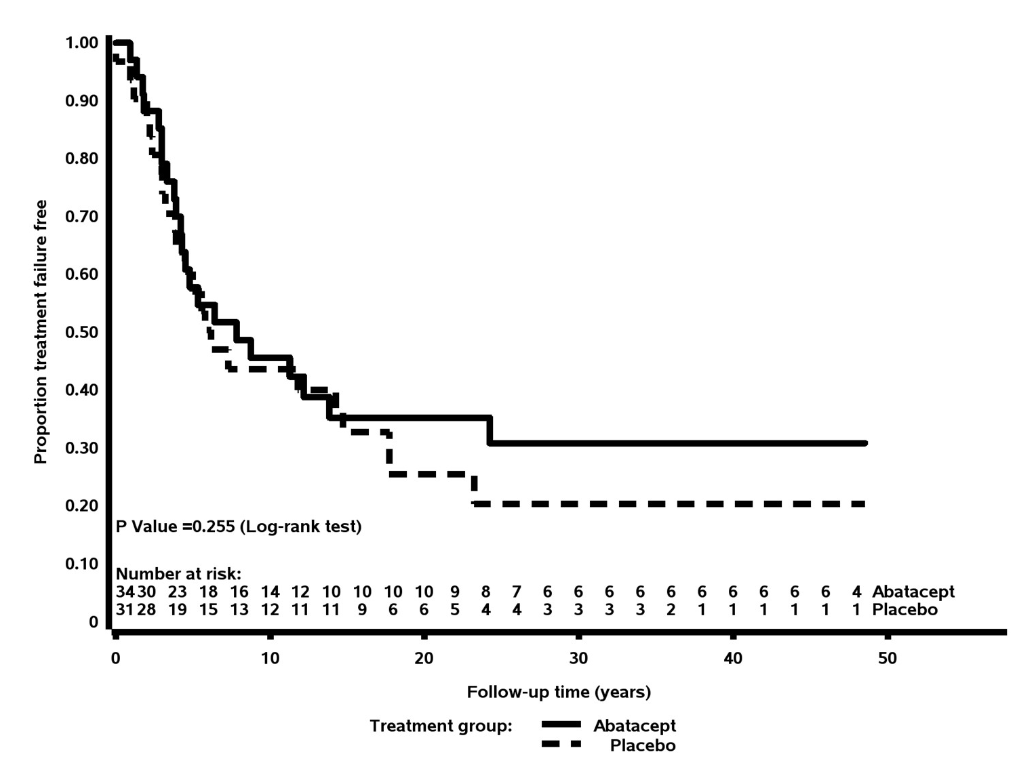

Langford et al. Abatacept NOT effective in GPA in ABROGATE RCT. 65 patients. Relapse/worsening in 62% vs 68%. No difference in any secondary end-point. @RheumNow #ACR24 Abstr#0823 https://t.co/yRFZ2diJFF https://t.co/LgXkPnDArE

Links:

Richard Conway RichardPAConway ( View Tweet)